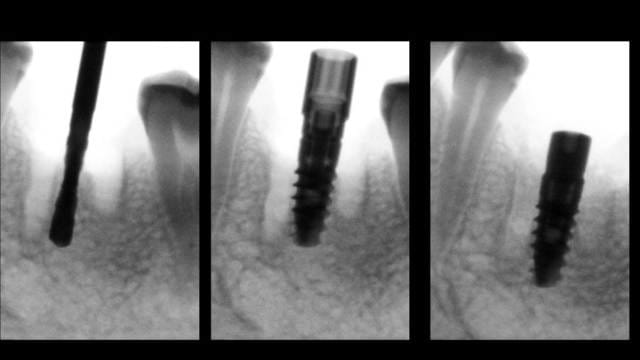

Cookie Consent byPrivacyPolicies.comInsertion immediate au niveau de 46 dans le septum - Eugenol

Insertion immediate au niveau de 46 dans le septum

Ici l'EII (extraction implantation immédiate) n'était pas indiquée à mon avis. Risque d'échec augmenté (suture ouverte) pour aucun bénéfice pour le patient.

Extraction, pose à 45 jours, implant plus large bien centré (meilleur profil d'émergence = hygiène facilitée).